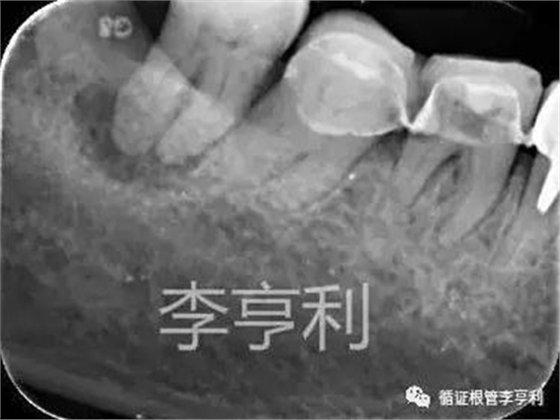

術(shù)前片 (2017-05-16)

輔助檢查:遠(yuǎn)中角度投射根尖片,見斷械影像移向近中,故判斷器械分離于近中頰根,根尖周未見明顯異常 。

遠(yuǎn)中角度投射,紅色箭頭為分離器械 (2017-05-16)

對于術(shù)前根尖片,臨床醫(yī)生一定要有足夠的風(fēng)險評估。例如該46,片子上根管影像不清晰,提示根管內(nèi)可能出現(xiàn)鈣化導(dǎo)致細(xì)窄;且近中根彎曲度明顯。因此,雖然該牙為活髓牙治療,但難度仍然較高,務(wù)必在開始治療之前一定要充分和患者解釋可能出現(xiàn)的根管堵塞、偏移、側(cè)穿、和器械分離等并發(fā)癥,讓患者了解相關(guān)的風(fēng)險;